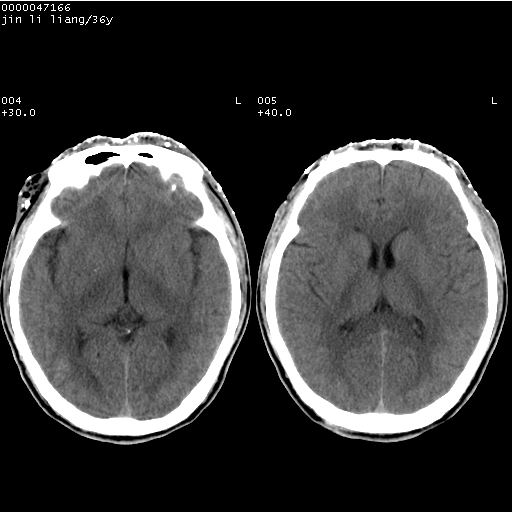

左眼球内容物浑浊其内见气体影,头面部异物.

左眼球破裂并异物,眶周、额顶部头皮及软组织挫伤并异物

迎面一炮,满脸开曝。额顶部头皮及软组织挫伤并异物,左眼球破裂积气并异物,典型的面目全非,惨不忍睹。

左眼球破裂积气并异物,眶周、额顶部头皮及软组织挫伤并异物,右侧眼环前内分异物